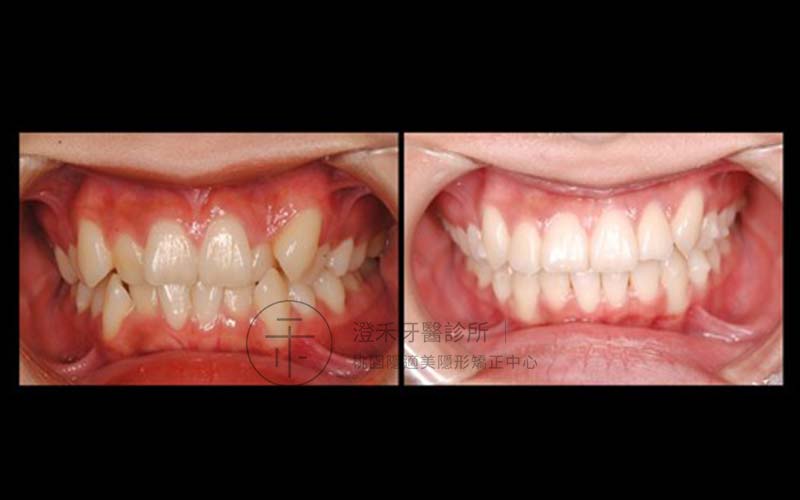

案例四

19歲,學生,牙弓窄沒有多餘空間使牙齒正常發育,造成齒列擁擠,使前牙牙齒有些旋轉及前後交疊。牙齒凌亂的情況下,會有許多死角不易清潔,長期下來容易造成蛀牙。不僅清潔不易,還會影響美觀。雙重情況下,透過矯正方式。翁同學經過數月與診所配合,牙齒排列整齊了,口腔照護也變得方便許多,重點是笑起來變得更甜更美!